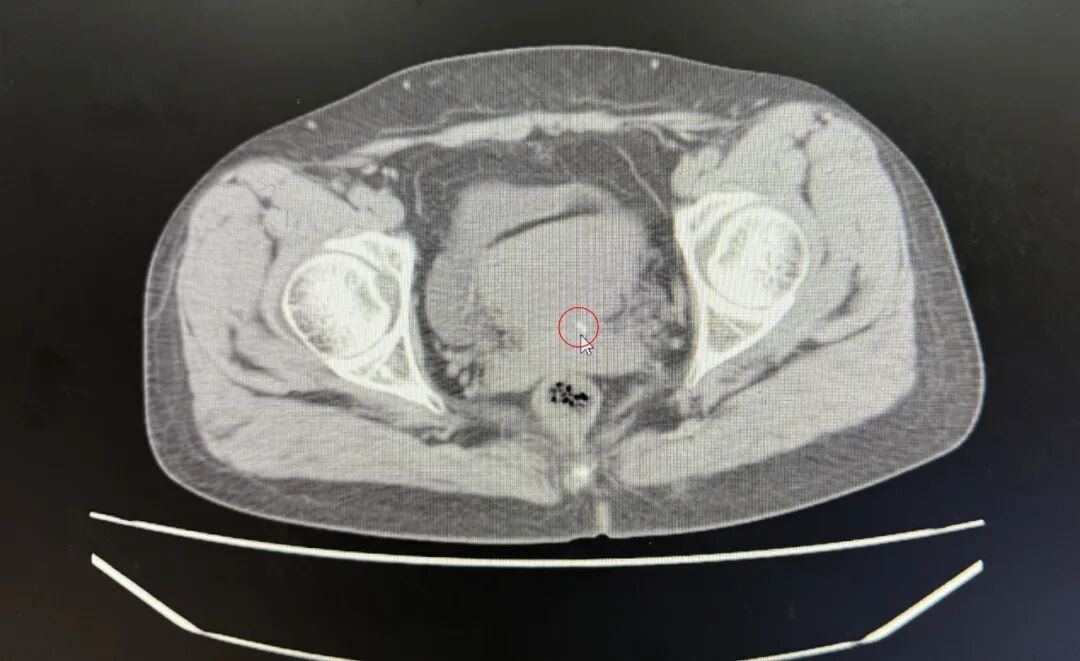

多家醫(yī)院取環(huán)失敗,殘端長進(jìn)肉里,直到...